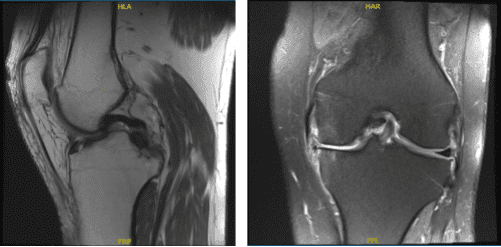

RM-3T: rodilla izquierda sin contraste.

La paciente es una mujer de 57 años que ha sido vista varias veces por dolor en la parte interna de la rodilla izquierda. Habíamos hablado sobre alternativas terapéuticas. El tratamiento no quirúrgico en forma de fisioterapia y antiinflamatorios no benefició al paciente. Se realizó una resonancia magnética, que reveló un desgarro en el menisco medial así como una posible afectación de la raíz de la rodilla izquierda.

El endoscopio se trasladó al compartimento tibiofemoral medial, donde se revelaron alteraciones osteoartriticas de grado 4 en la mayor parte del cóndilo femoral medial, así como una compleja ruptura a lo largo del cuerpo y el cuerno posterior del menisco medial.